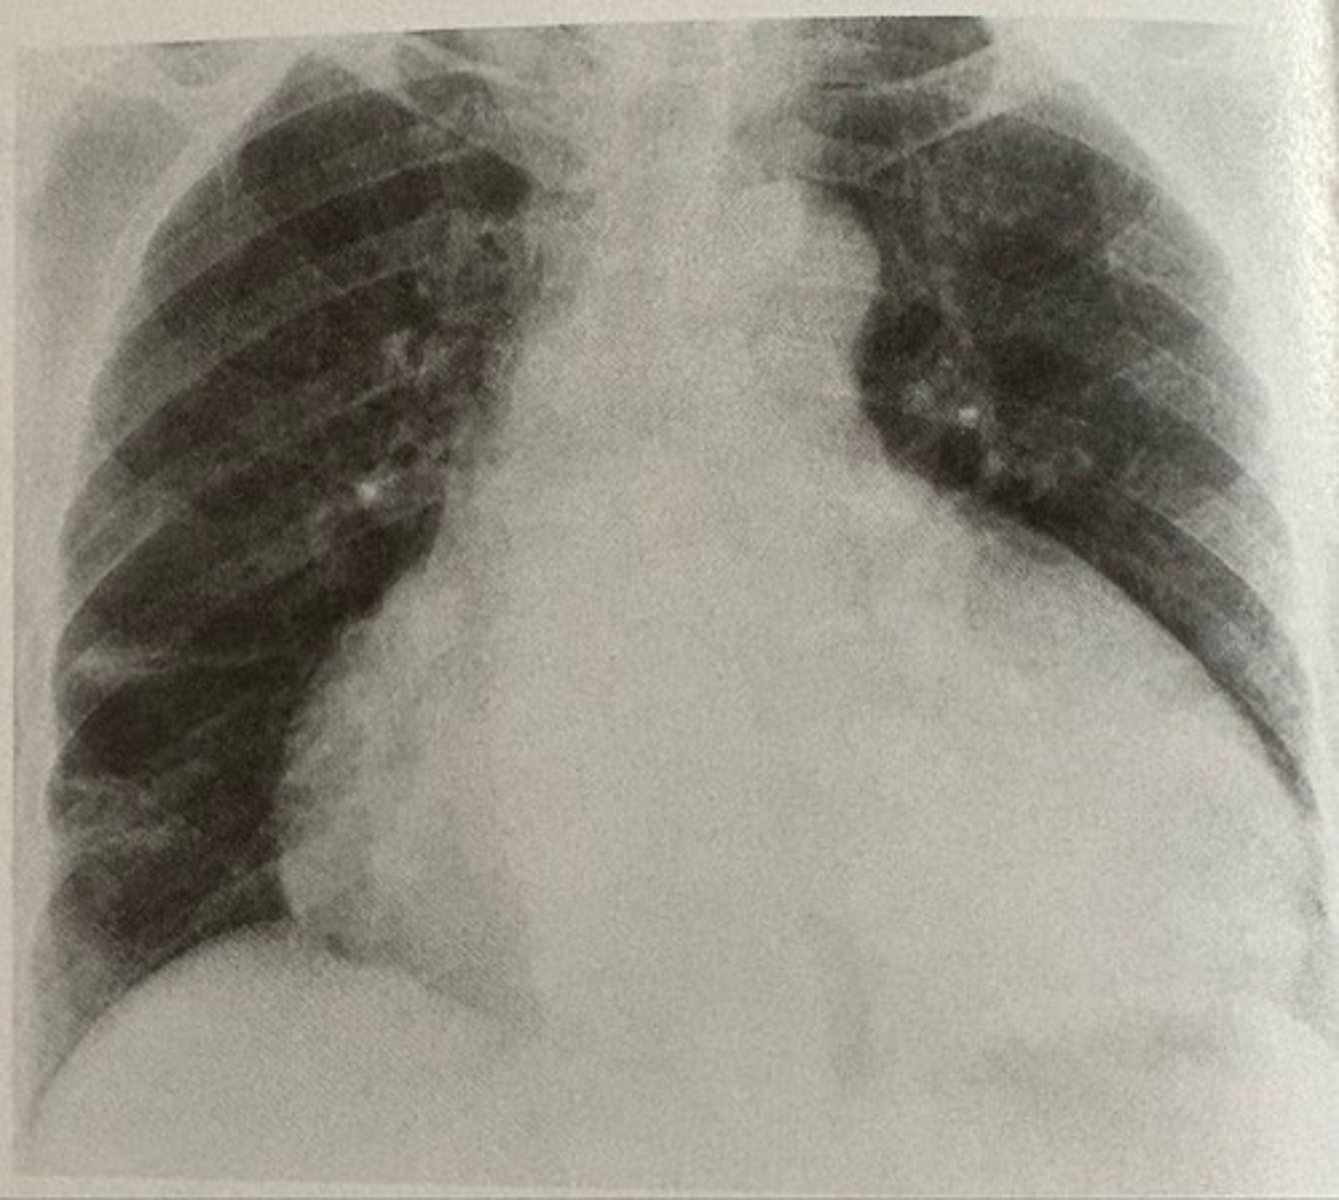

butterfly pattern of severe pulmonary edema

what pathology is present?